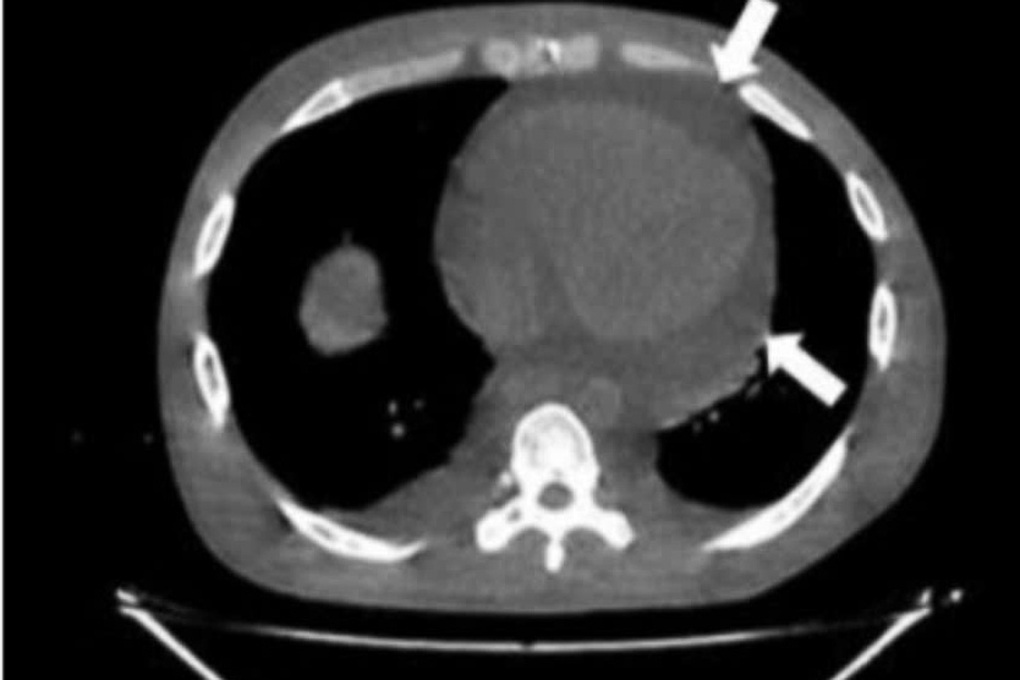

Sáng 18/9, Bệnh viện Hữu Nghị (Hà Nội) tiếp nhận nữ bệnh nhân 29 tuổi trong tình trạng choáng ngất, được người nhà đưa vào cấp cứu.Qua khám sơ bộ, các bác sĩ ghi nhận bệnh nhân da xanh, niêm mạc nhợt, mạch nhanh, huyết áp tụt, nghĩ nhiều đến sốc mất máu.Đây là ca bệnh trẻ, tình trạng nguy kịch, ê-kíp cấp cứu lập tức triển khai hồi sức tuần hoàn, truyền dịch, thở oxy, làm các xét nghiệm chẩn đoán song song.Người nhà cho biết, bệnh nhân đại tiện phân đen từ hôm trước, mệt lả, mới nghỉ việc ở nhà...